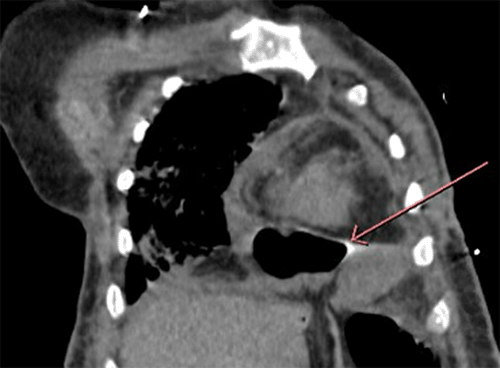

Upon arrival, the patient had diffuse abdominal pain and obstructive symptoms. Vital signs were temperature of 95.9°F, sinus tachycardia with a rate of 124 beats per minute, blood pressure 88/60mmHg, respiratory rate of 30, and 97% SaO2 on 4L nasal cannula. Given her change in exam, repeat imaging was obtained to assess for abdominal pathology. Repeat imaging revealed parietopericardial herniation, which contained small bowel (Figure 1 to Figure 3). A small number of ascites was noted on CT. Broad-spectrum antibiotics and fluid resuscitation were initiated, and acute care surgery was consulted. Her lab work was notable for worsening leukocytosis, liver function tests concerning for shock liver, acute kidney injury, and elevated INR (Figure 1).

Figure 1. Coronal CT Image Herniation of Small Bowel Herniation into Pericardial Space. Published with Permission

Arrow pointing to pericardial and small bowel interface.